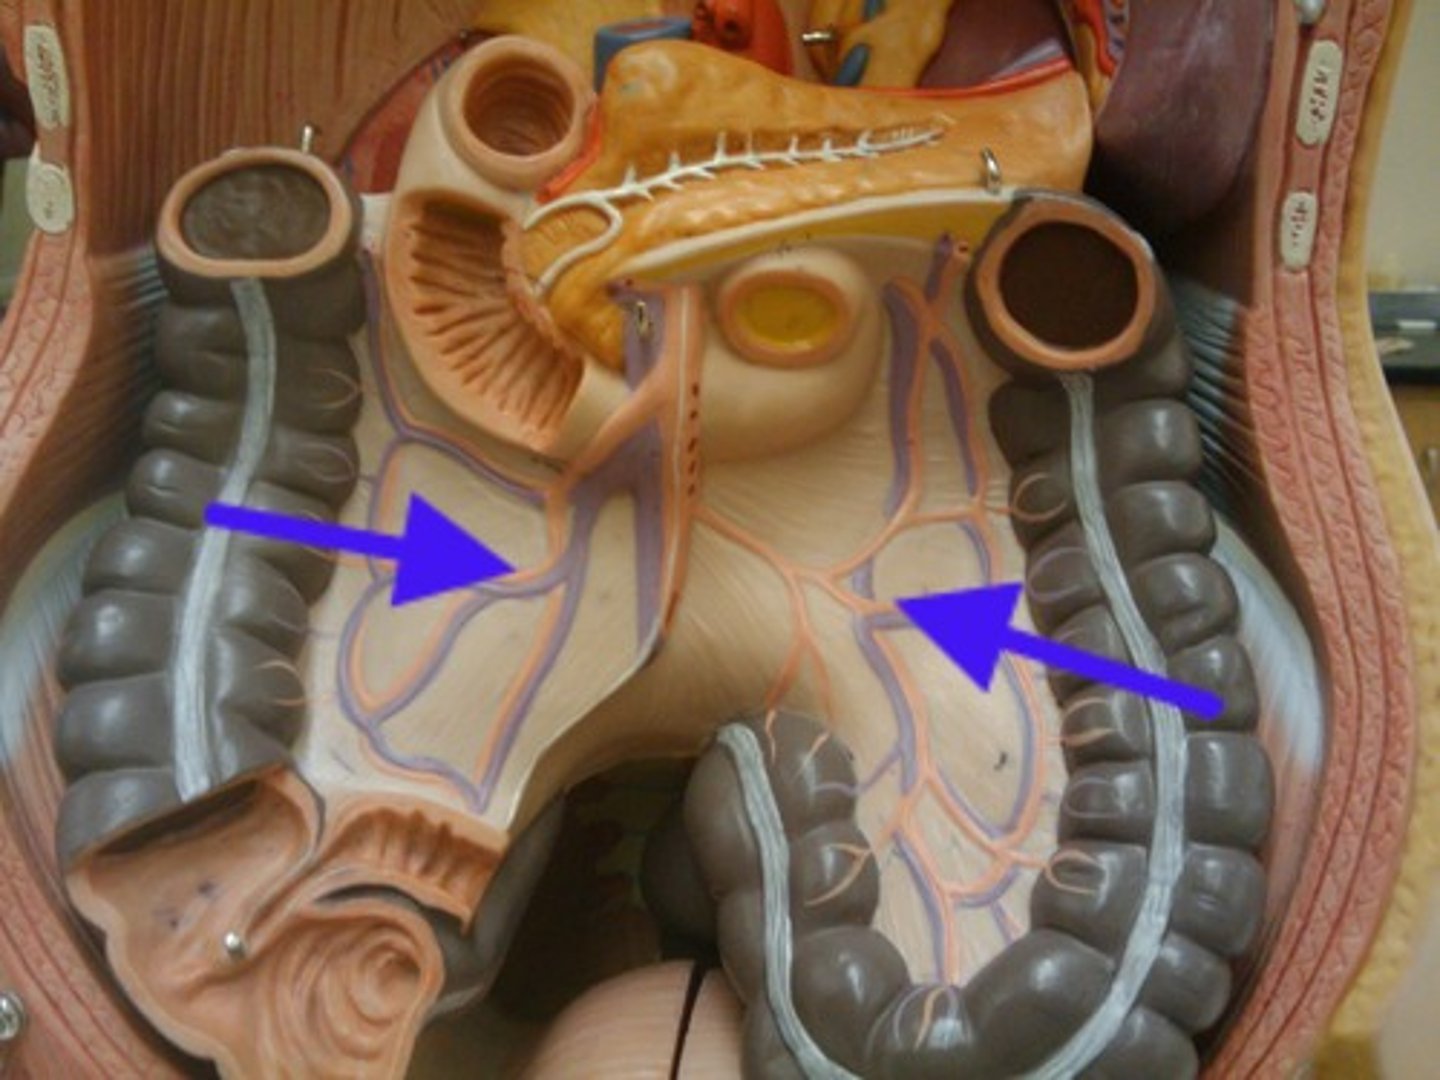

mesentery

taeniae coli